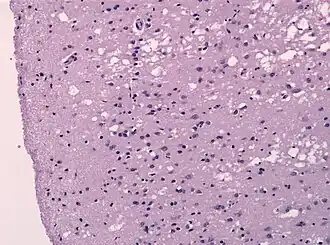

![]() Гистологический препарат — ткань лобной доли головного мозга больного болезнью Крейтцфельдта — Якоба | |

Прионы вызывают нейродегенеративные заболевания, так как образуют внеклеточные скопления в центральной нервной системе и формируют амилоидные бляшки, которые разрушают нормальную структуру ткани. Разрушение характеризуется образованием «дыр» (полостей) в ткани, и ткань принимает губчатую структуру из-за формирования вакуолей в нейронах[68]. Другие наблюдаемые при этом гистологические изменения — астроглиоз (увеличение численности астроцитов из-за разрушения близлежащих нейронов) и отсутствие воспалительных реакций[69]. Хотя инкубационный период прионных заболеваний, как правило, очень долог, после появления симптомов болезнь прогрессирует быстро, приводя к разрушению мозга и смерти[70]. Проявляющимися при этом нейродегенеративными симптомами могут быть конвульсии, деменция, атаксия (расстройство координации движений), поведенческие и личностные изменения.